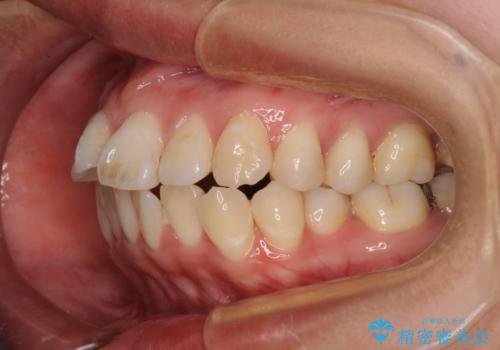

- 上下の出っ歯を気にして来院された患者様です。

口元を積極的に引っ込めるために、上下左右の第一小臼歯を4本抜歯することとしました。

また、上下前歯は舌の突出癖による開咬となっていたため、舌のトレーニングを徹底するよう指示しました。

舌突出癖の改善トレーニングは、仕上がり、治療期間、そして治療後の後戻りに大きな影響を及ぼします。

トレーニングをしっかりと行っていただいたため、スッキリとした口元に仕上がりました。